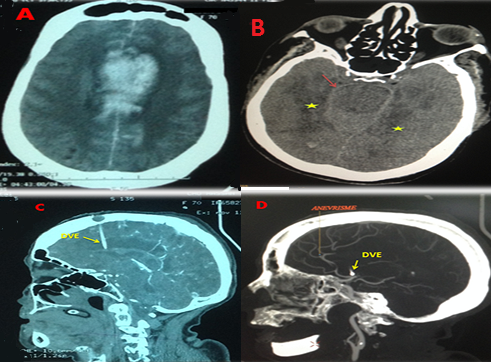

Il s'agit d'une patiente de 70 ans, diabétique sous insulinothérapie, admise aux urgences en troubles de conscience. Le scanner cérébral à son admission a montré une hémorragie méningée grade IV de WFNS grade 4 de Fisher avec inondation ventriculaire et hydrocéphalie (A). La patiente a bénéficié d'une dérivation ventriculaire externe. L'angioscanner cérébral (B, C, D) réalisé à H24 a objectivé une persistance de l'hémorragie méningée avec inondation ventriculaire (B), un accident vasculaire ischémique dû au vasospasme dans les territoires des artères cérébrales antérieures et postérieures en bilatéral (B, C) et un petit anévrysme de l'artère cérébrale antérieure de 3 millimètres (D). Les vélocités moyennes au doppler transcrânien étaient élevées (210 cm/s). La prise en charge thérapeutique associait nimodipine en perfusion continue, hyperventilation et « triple-H thérapie». L'évolution était fatale par l'installation rapide d'une défaillance multiviscérale. Le vasospasme qui suit l'hémorragie méningée anévrismale est une pathologie complexe à l'étiologie multifactorielle. Défini comme une réduction de la lumière d'une artère conductrice dans l'espace sous-arachnoïdien associée à des troubles de la microcirculation, il survient classiquement dès le troisième jour et jusqu'à la quatrième semaine après l'hémorragie méningée. L'observation d'un vasospasme ultraprécoce a valeur de resaignement et serait prédictif d'une lourde morbi-mortalité. Il peut conduire à des « déficits neurologiques ischémiques retardés » et parfois au décès. Le traitement préventif repose sur la nimodipine et une fois le vasospasme avéré et l'anévrysme sécurisé, la « triple-H thérapie » (hypervolémie, hypertension artérielle et hémodilution) est préconisée.